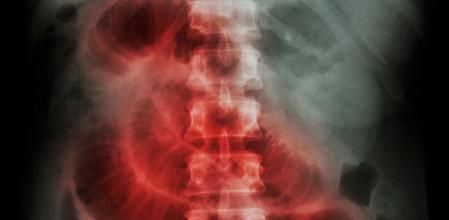

La radiografía muestra una obstrucción del intestino delgado

El examen físico y las radiografías de abdomen suelen ser las pruebas básicas para confirmar la obstrucción. También se puede realizar tomografía computerizada abdominal (TC), enema opaco (radiografía de colon y recto), y radiografías de tránsito esofagogastroduodenal (radiografías del esófago, estómago e intestino delgado). Si hay estrangulación será necesaria una laparatomía exploratoria (exploración quirúrgica del abdomen). En el caso de los niños lo habitual es realizar una ecografía.